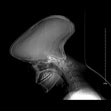

标题: 患者体形正常,副鼻窦冠状位扫描前,扫描定位片,请各位

重新扫描定位片正常,是图像采集系统还是图像重建系统故障

机器无故障。是病人动了

典型的运动伪影.

是的,是扫定位图期间,病人动了。

是典型舟状头畸形,其原因是婴儿在颅脑发育时期失状缝过早闭合,而冠状缝和人字缝没闭合所造成的颅脑先天发育畸形,与塔状头畸形正好相反,塔状头畸形是冠状缝和人字缝过早闭合,而失状缝没闭合正常发育所造成,

运动伪影,颅骨的三层结构很清晰???

如果只是这一病人,应该是动了.如果图象都是这样就是图像采集系统问题.

哈哈,是典型的扫描时运动伪影,经常碰到这样的病人。